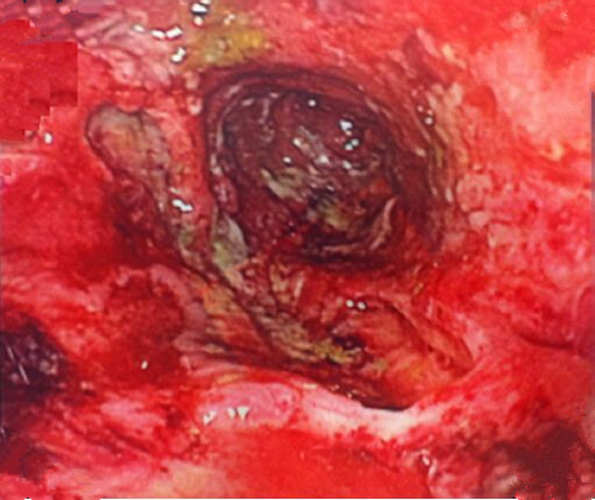

嚴重慢性結腸炎的

嚴重慢性結腸炎腐爛的

早期慢性結腸炎的